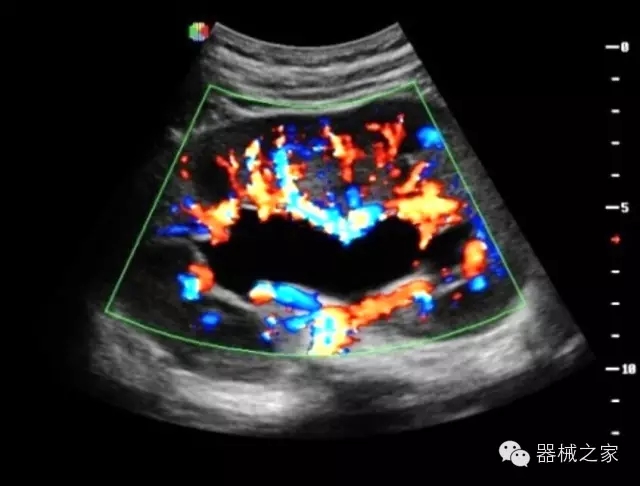

臨床圖片賞析

·獨(dú)有RF敏感血流使得心臟血流完美呈現(xiàn);